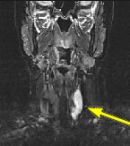

Fig.1 Fig.2 Fig.3 Fig.4

FINDINGS: The ultrasound (not shown) revealed a large solid mass behind the left lobe of the thyroid. Fig. 1-2 are MRI images of the neck demonstrating a mass behind the left thyroid lobe with hyperintensity on T2 weighted and STIR images (Fig. 1, 2 top) and enhancement higher than the thyroid (Fig. 2 bottom). Fig. 3-4 are Sestamibi images with Fig. 3 being coronal (top) and axial (bottom) SPECT images and Fig. 4 the early and delayed static images demonstrating persistent activity in the mass on delayed images while the thyroid activity washes out (arrows).